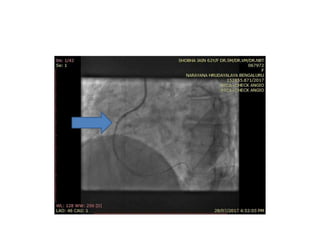

• 62 yr old lady

• Diabetic /HTN

• P/W NSTEMI

• ECHO – INFERIOR WALL HYPOKINESIA EF 45%

• CAG – LAD prox- 80% near the bifurcation with

D1 and tubular 70-80% lesion at proximal RCA

• PLAN – RADIAL ROUTE PTCA TO LAD & RCA